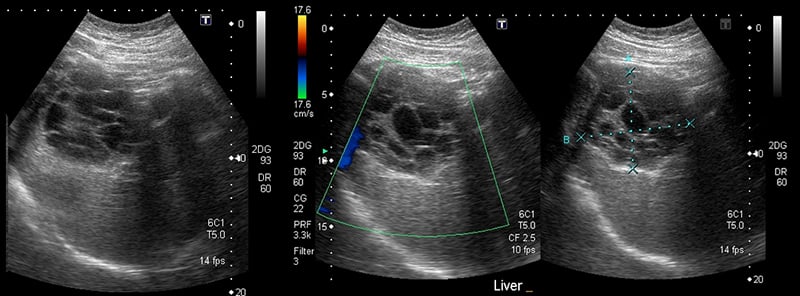

- Enlargement of portal vein (>14mm)

Figure 16. Dilated portal vein (>14mm) in the setting of portal hypertension.

- Reversal of portal venous flow

- Physiologic blood flow in the portal vein is from deep (the spleen and intestines) to superficial (the liver periphery), towards the probe.

- With the probe on the anterior abdominal wall, blood in the portal vein flows from central (the mesenteric and splenic veins) towards the liver and will be red when color Doppler is applied. The middle and left portal venous branches will still appear red. However, blood in the right portal venous branch will flow deep into the right lobe, appearing blue.

Figure 17. Color Doppler image with arrows illustrating normal portal venous blood flow, from the center towards the periphery of the liver.

- May indicate portal hypertension, as increased pressure forces blood back towards the spleen and intestines

- Blue flow (away from probe) in the portal vein on color Doppler.

- Color Doppler may serve as a useful screening tool.